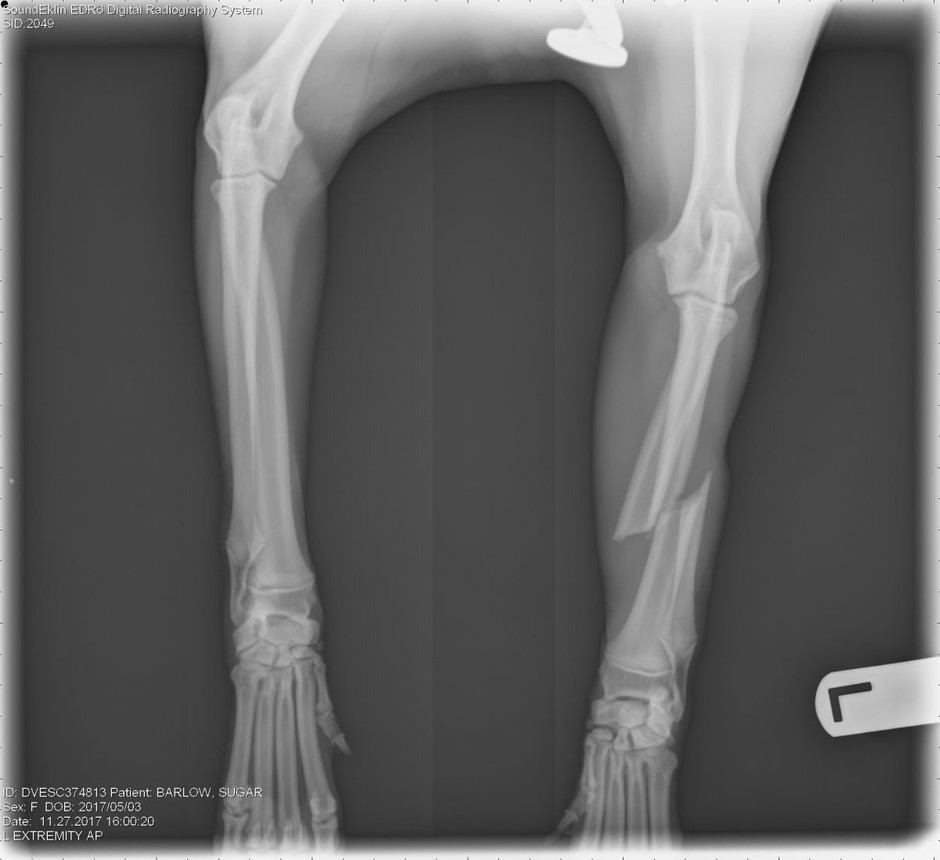

Sugar is a 7 month old Blue Heeler (Australian Cattle Dog). While playing a morning game of Frisbee, sugar severely broke her leg. She completely broke her radius and ulna of her front left leg. In order to save her leg, we need to come up with a minimum of $3,000 to cover the upfront cost for the surgery.

ANY help is beyond appreciated! Thank you for taking the time to read about Sugar's need for Funds. I have included pictures of her X-Rays and Sugar, below.